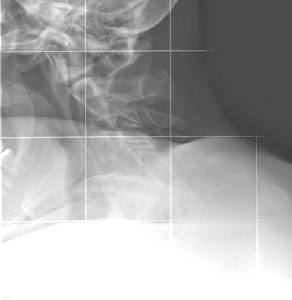

Heute habe ich wegen der häufigen Nackenverspannung und Ohrgeräuschen auf Anraten eines Manualtherapeuten HWS Aufnahmen machen lassen.

Ich habe eine HWS Kyphose, bei gleichzeitig bekannten Flachrücken, was offensichtlich zusammenhängt. Nun ist mir so einiges klar.